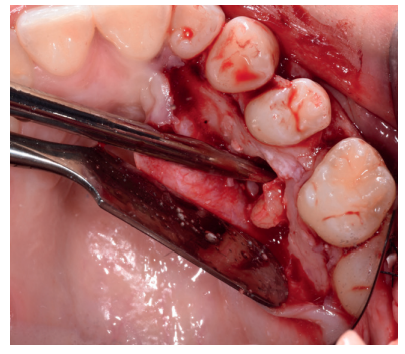

Caso clínico: se presenta un caso clínico de una mujer de 20 años, sin antecedentes médico-quirúrgicos de interés, que acudió a consulta remitida por su ortodoncista, para la extracción de un premolar maxilar retenido, en posición invertida. Tras la extracción del premolar y del tercer molar inferior retenidos, se obtuvo dentina procedente de ambos, para la regeneración ósea guiada del defecto resultante de la extracción del premolar, realizando revisiones a la semana y a los 4 meses de la intervención.

Clinical case: a clinical case of a 20-year-old woman is presented, with no interesting medical record, who went to dental clinic for removal of an inverse maxillary bicuspid retained. After maxillary bicuspid and lower third molar extractions, autogenous dentin was obtained from both teeth, to perform a guided bone regeneration of the bicuspid defect. A week and 4-month check-up were carried out.